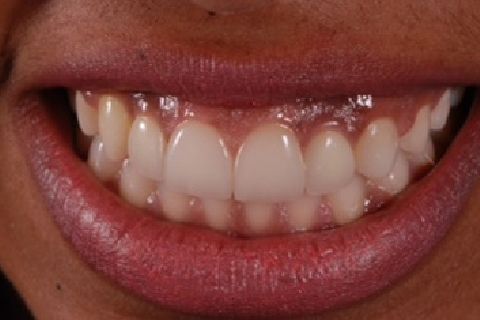

''Neste caso, a paciente gostaria de melhorar a estética do seu sorriso, prejudicada pela agenesia de ambos os incisivos laterais superiores. Devido à baixa disponibilidade óssea, observada na tomografia computadorizada, optou-se pela instalação de implantes estreitos (Xive – Dentsply Implants – 3.0 mm de diâmetro) com regeneração simultânea (Biooss e Biogide – Geistlich), ao invés de realizar enxerto ósseo prévio. Após osseointegração, foi realizado condicionamento gengival com provisórios e novo enceramento diagnóstico. O caso foi finalizado com coroas livres de metal sobre os implantes e microlaminados cerâmicos sobre os incisivos centrais (e.max - dissilicato de lítio – Ivoclar Vivadent), visando o mínimo desgaste de estrutura dental sadia. ''